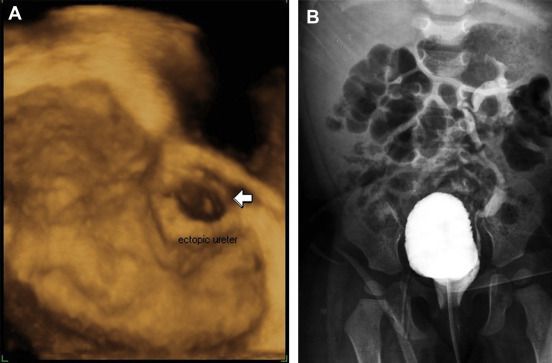

Golf hole orifice of ureter in ureter tuberculosis, associates with vesicoureteral reflux.A retracted funnel-shaped condition of the ureteral orifice in the wall of the bladder.